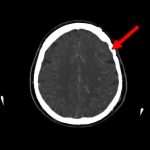

断層撮影

手術前1